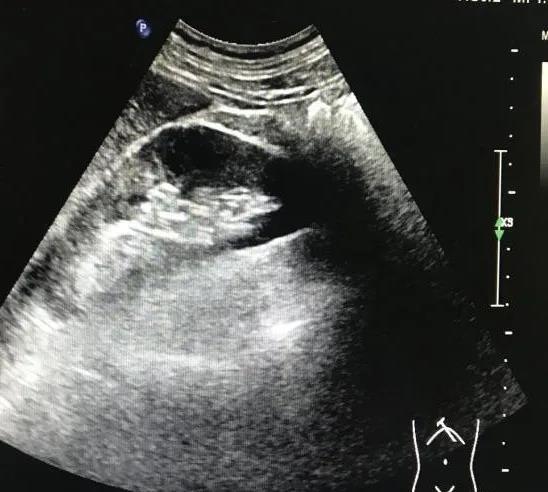

最后我們來(lái)看一個(gè)典型病例。患者男性29歲,打籃球大量飲水1小時(shí)后左側(cè)腰背部突發(fā)劇烈疼痛,為絞痛,同時(shí)伴血尿,急診速來(lái)我院就醫(yī),行泌尿系彩超可見(jiàn)雙腎大小、形態(tài)尚可,被膜尚連續(xù),左腎竇內(nèi)探及一枚強(qiáng)回聲光團(tuán),大小約1.7x1.2cm,后方伴聲影(見(jiàn)圖3),左側(cè)腎盂回聲分離,右側(cè)腎臟未見(jiàn)明顯異常(見(jiàn)圖4)。實(shí)驗(yàn)室尿常規(guī):紅細(xì)胞滿(mǎn)視野,白細(xì)胞2-3/HP,其余陰性。綜合以上考慮為左腎結(jié)石并輕度積水。

圖4:正常右腎